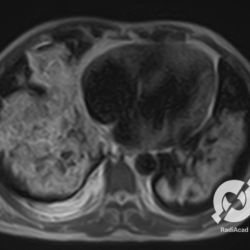

Lesões intersticiais reticulares difusas, aumento do volume cardíaco e inversão da circulação pulmonar (Rx)/ opacidades em vidro fosco e estruturas venosas calibrosas (TC).